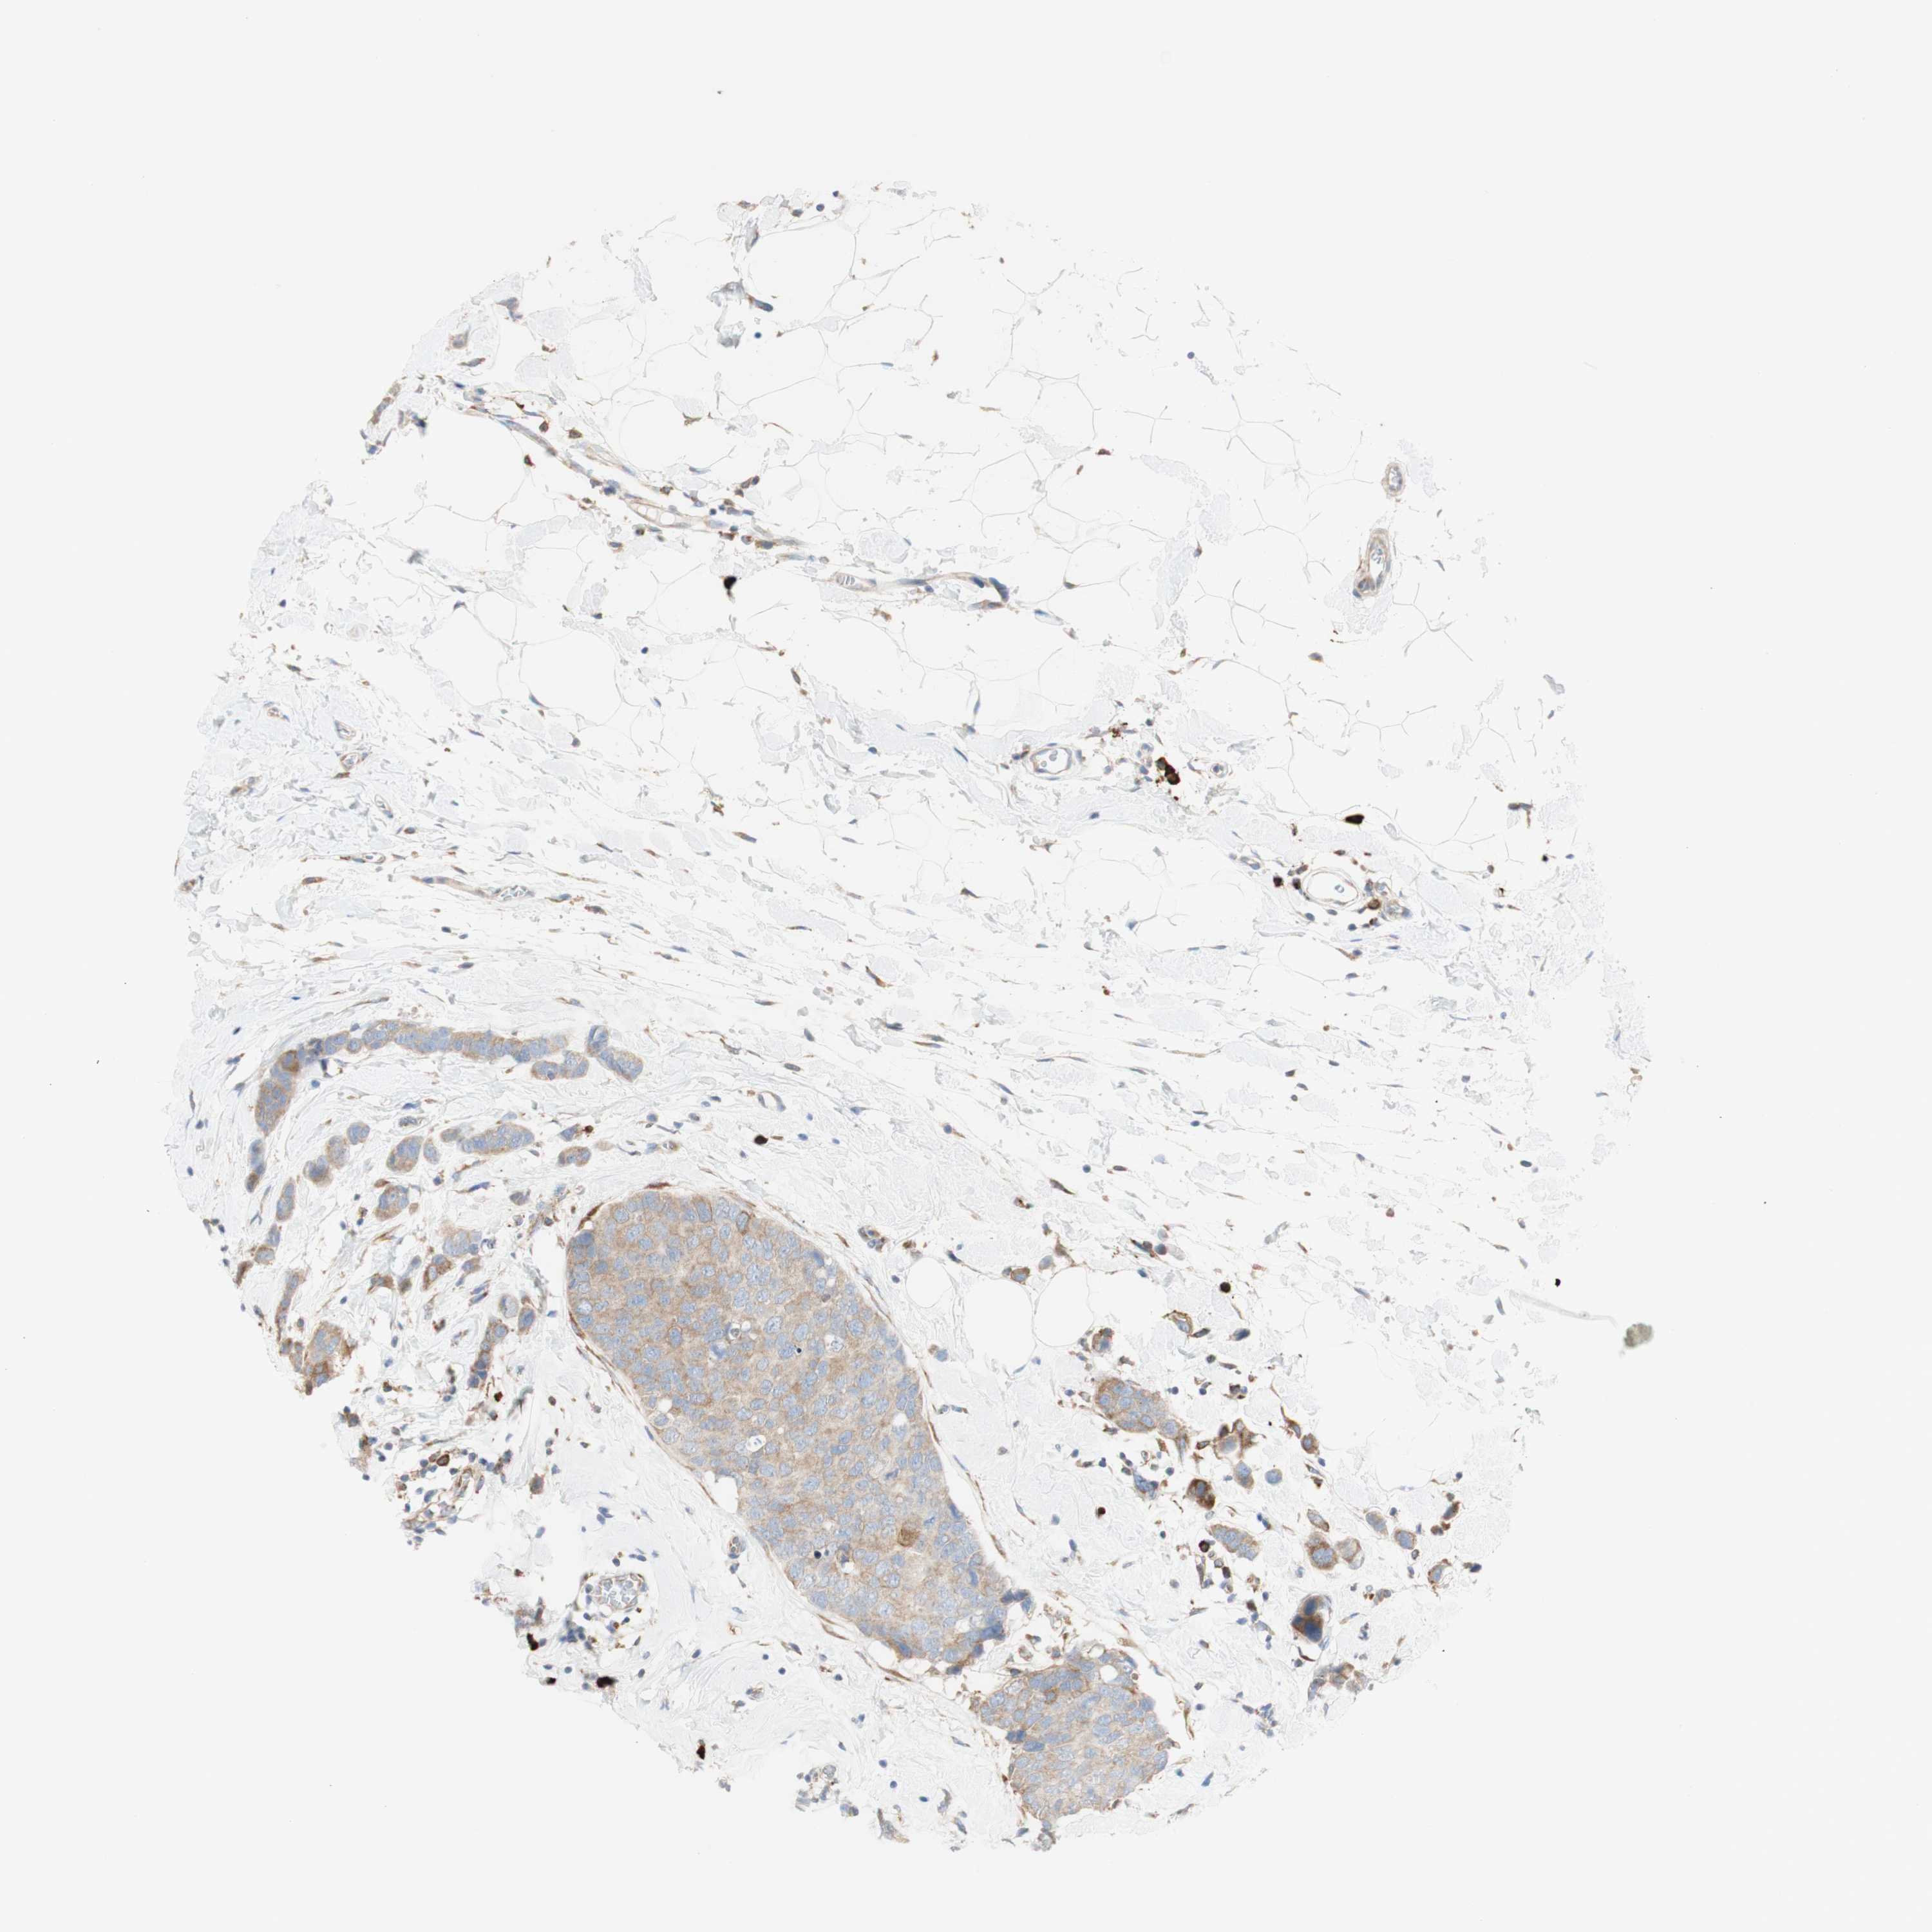

CANCER BREAST CANCER Show tissue menu

BRCA TCGA BRCA VALIDATION PROTEIN EXPRESSION

ANTIBODIES

AND

VALIDATION